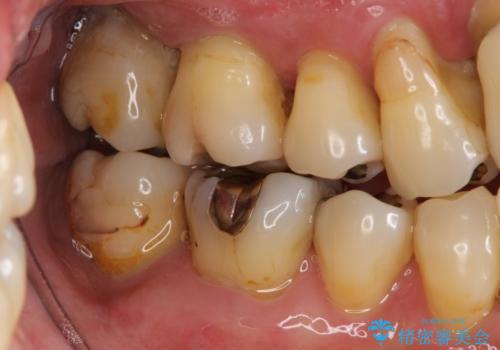

- 歯が全体的にグラグラし、しっかりと物が噛めなくなり歯周病治療を希望され来院されました。

残すことのできる歯、残すことのできない歯を初期治療を進めながら見極め、最終的に臼歯部はインプラント、上顎前歯は入れ歯による補綴計画となりました。